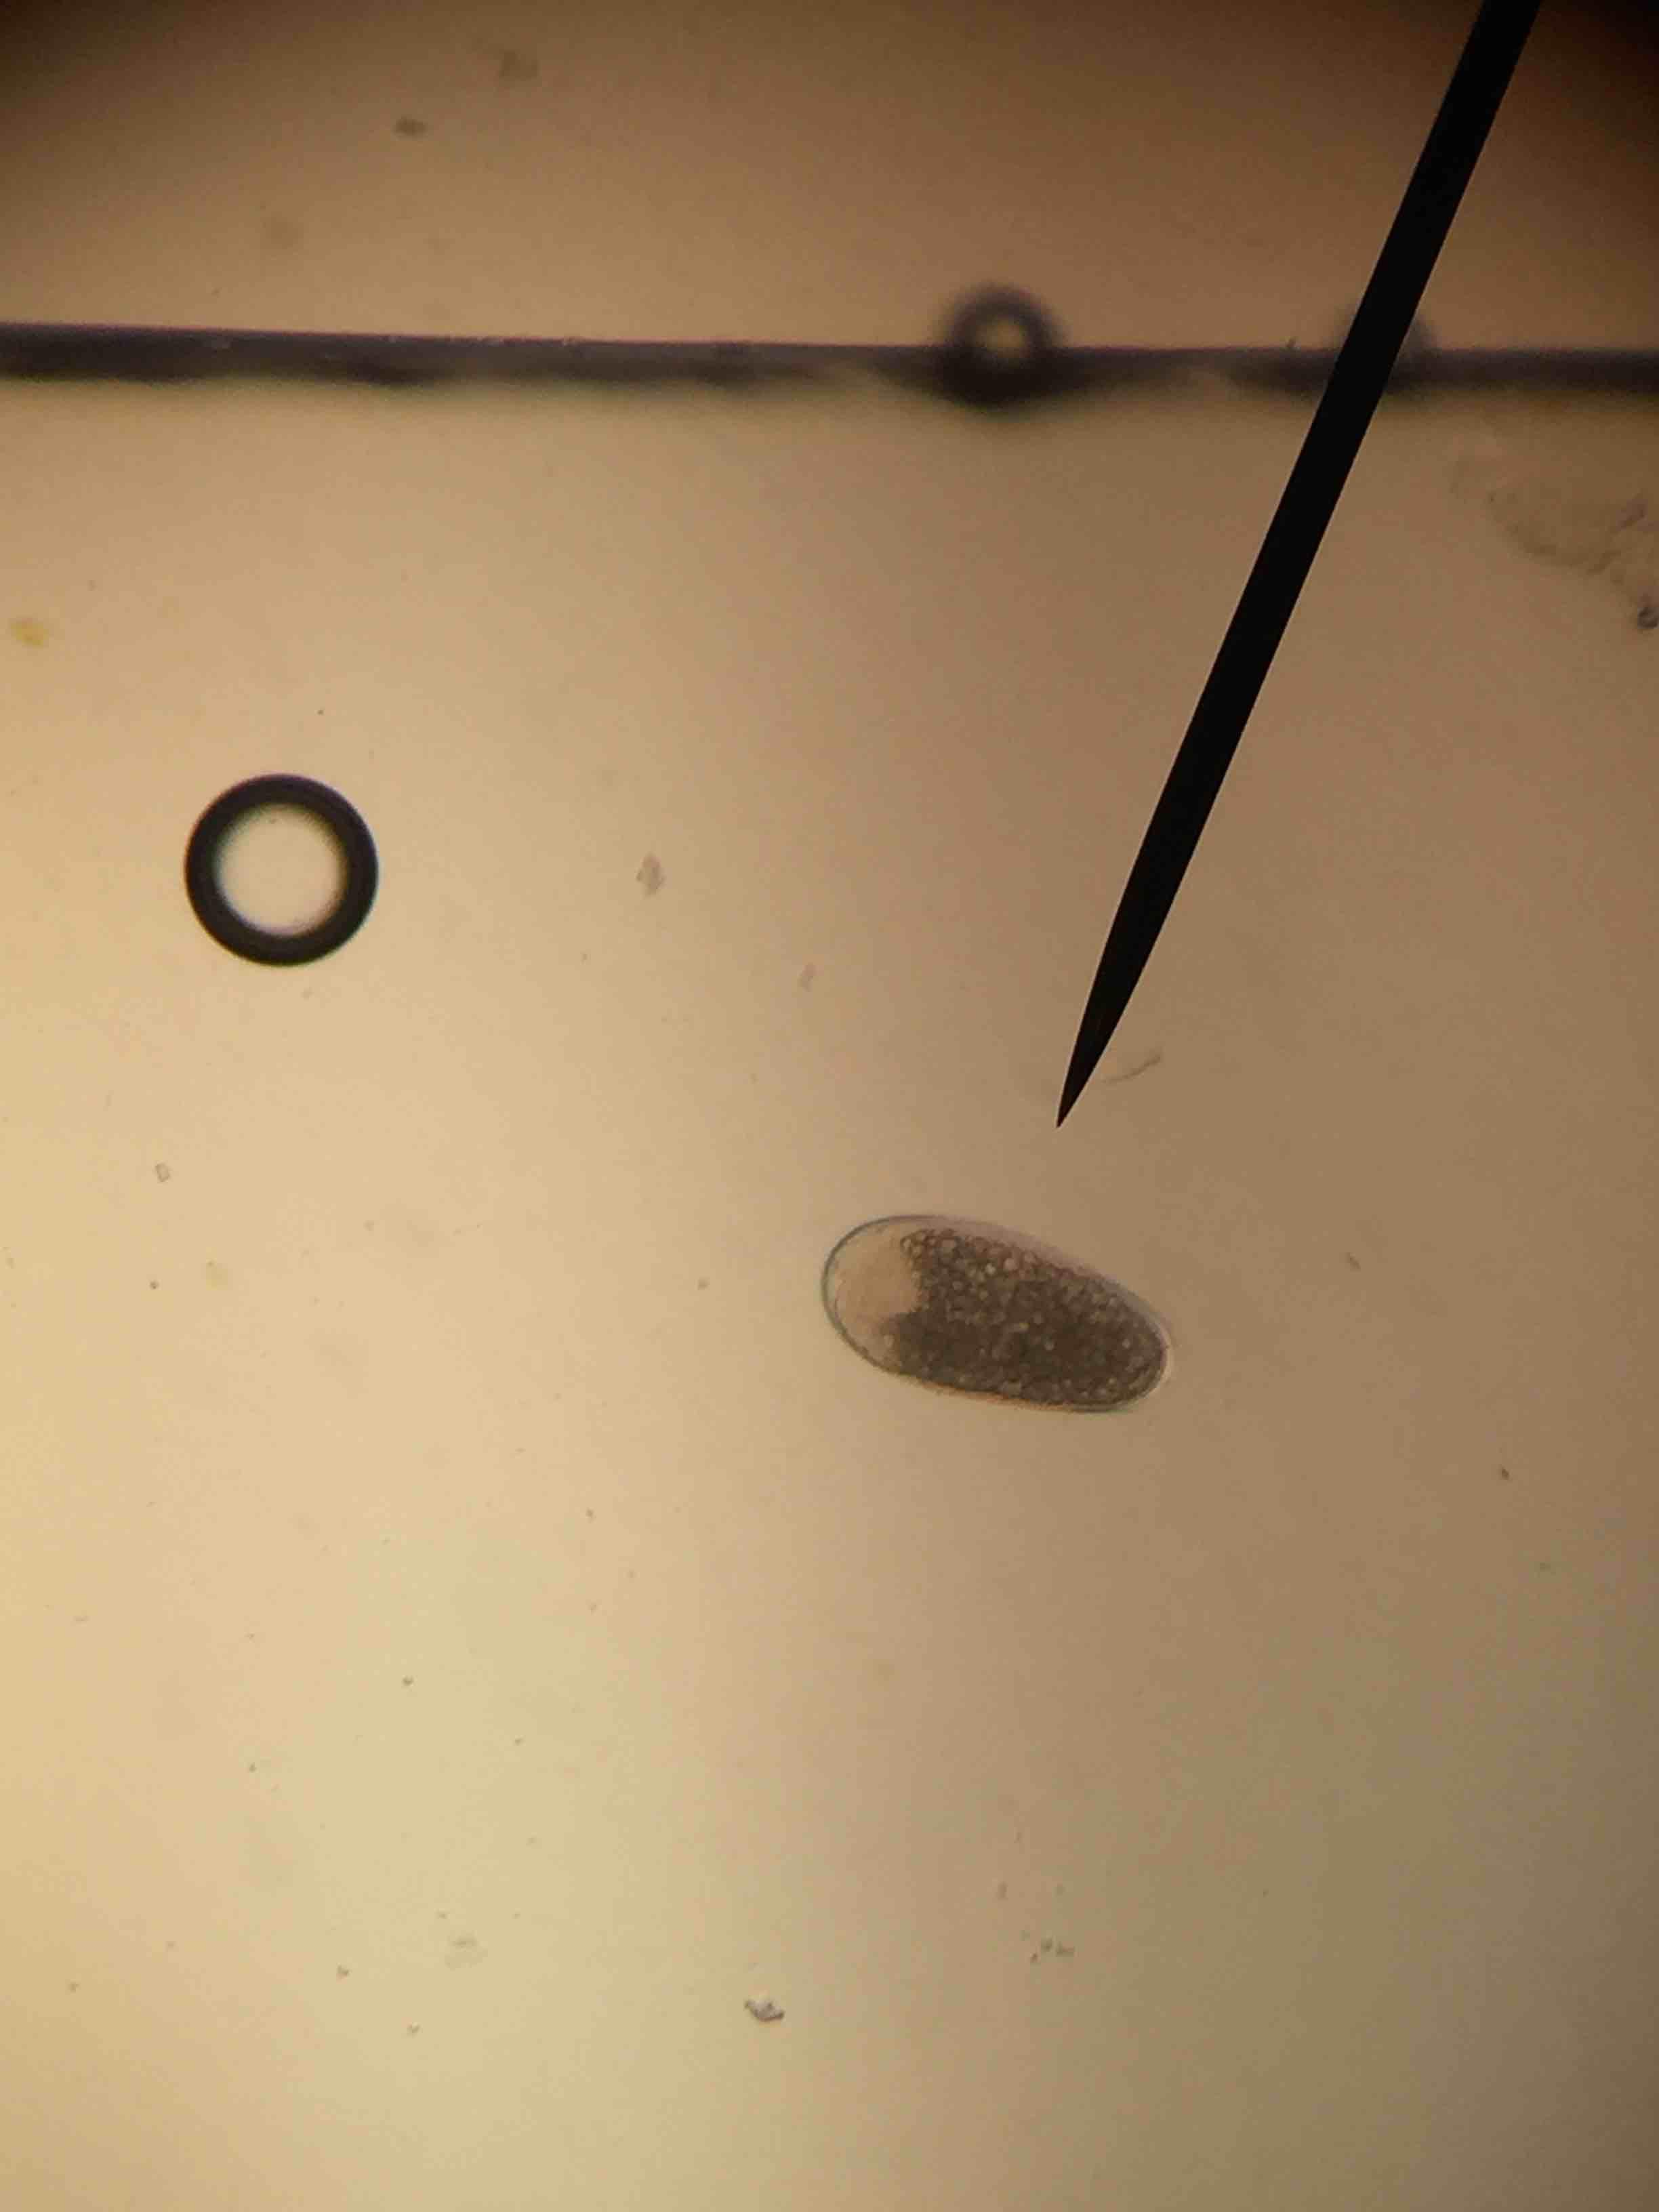

Ran a fecal on my puppy and saw this. Took him to the vet and he saw nothing and said it's not any parasite he recognizes. Just curious if anyone can identify?

Hello, It looks like a strongyle egg. It could be non-pathogenic if you're only seeing one egg. However, some plant material can also trick you and look like parasite eggs. The reason I say that is because that picture doesn't show an obvious operculum like strongyle eggs and the gravel is smaller than canine strongyle eggs. Hope this helps.